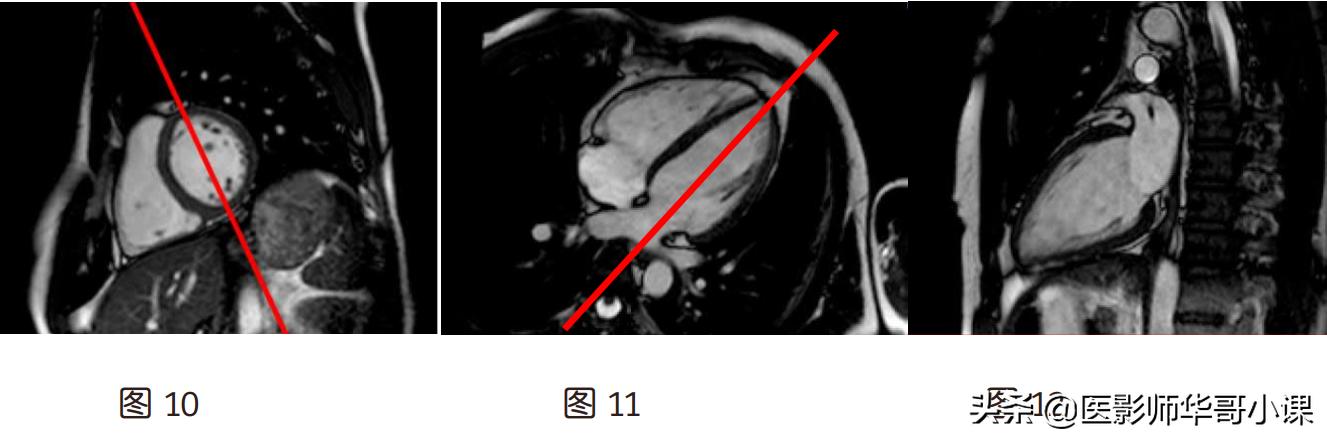

(3)四腔心(图 9):假两腔心上(图 7)定位线平行心尖到二尖瓣中点连线,左室乳头肌

肉层面短轴位(图 8)上平行左室中心到右室口的连线

(4)左两腔(图 12):左室乳头肌层面的短轴位(图 10)上定位线通过左室中心并与室间

隔平行,四腔心上(图 11)平行心尖到二尖瓣口中点的连线